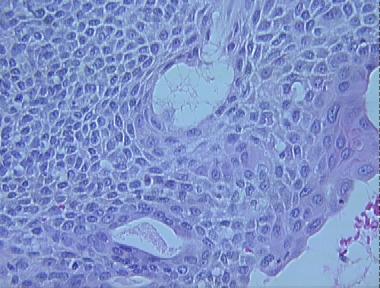

eccrine poroma

Histologic Features